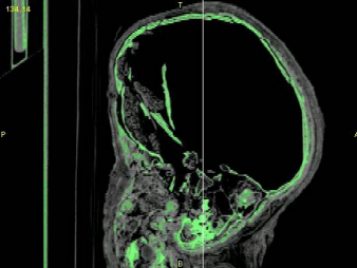

Now that I have the data, it is my responsibility to interpret it. I was fortunate enough to obtain powerful medical imaging software with a limited license and, with it, have started to build three-dimensional computer models. It is a surprisingly detailed process, and over the course of two weeks I have only been able to separate the legs and arms. Hopefully, within the bounds of my temporary software license I will be able to build an accurate representation of the skull and as much of the body as possible. These data sets will be saved in a format known as stereolithography (STL) data.

From these data, I will attempt to build accurate plastic representations of my computer models in what is known as a stereolithographic apparatus, or SLA. Under the guidance of Dr. Halloran, a model accurate to 13 nanometers should be producible. This model should provide scientists an accurate view of the child’s bones. From it, we will be able to study diet, age, and countless other aspects of the child’s life—all without ever touching the mummy.